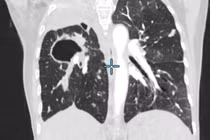

Can thiệp tắc mạch phế quản cứu bệnh nhân ho ra máu mức độ nặng, suy hô hấp

Ho ra máu mức độ nặng có thể dẫn đến tử vong do suy hô hấp hoặc mất máu nếu không được xử trí kịp thời.